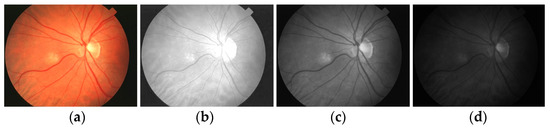

2.2. Color Space Selection and Noise Removal

The second preprocessing stage is the selection of suitable color channels for the extraction of retinal blood vessels. Figure 5 shows the color space extracted from the input image, i.e., the red, green, and blue channels. In this paper, I chose the green image because this color channel shows the detail of blood vessels and retinal information more than other channels do (see Figure 5c). Then, I used the default parameters of a median filter to suppress the noise in the improved image. The presence of noise in the retinal images was also removed to obtain a smooth image that was suitable for extracting the presence of the blood vessels.

Figure 5.

Retinal color space separation: (a) enhanced image, (b–d) RGB and individual space, respectively.